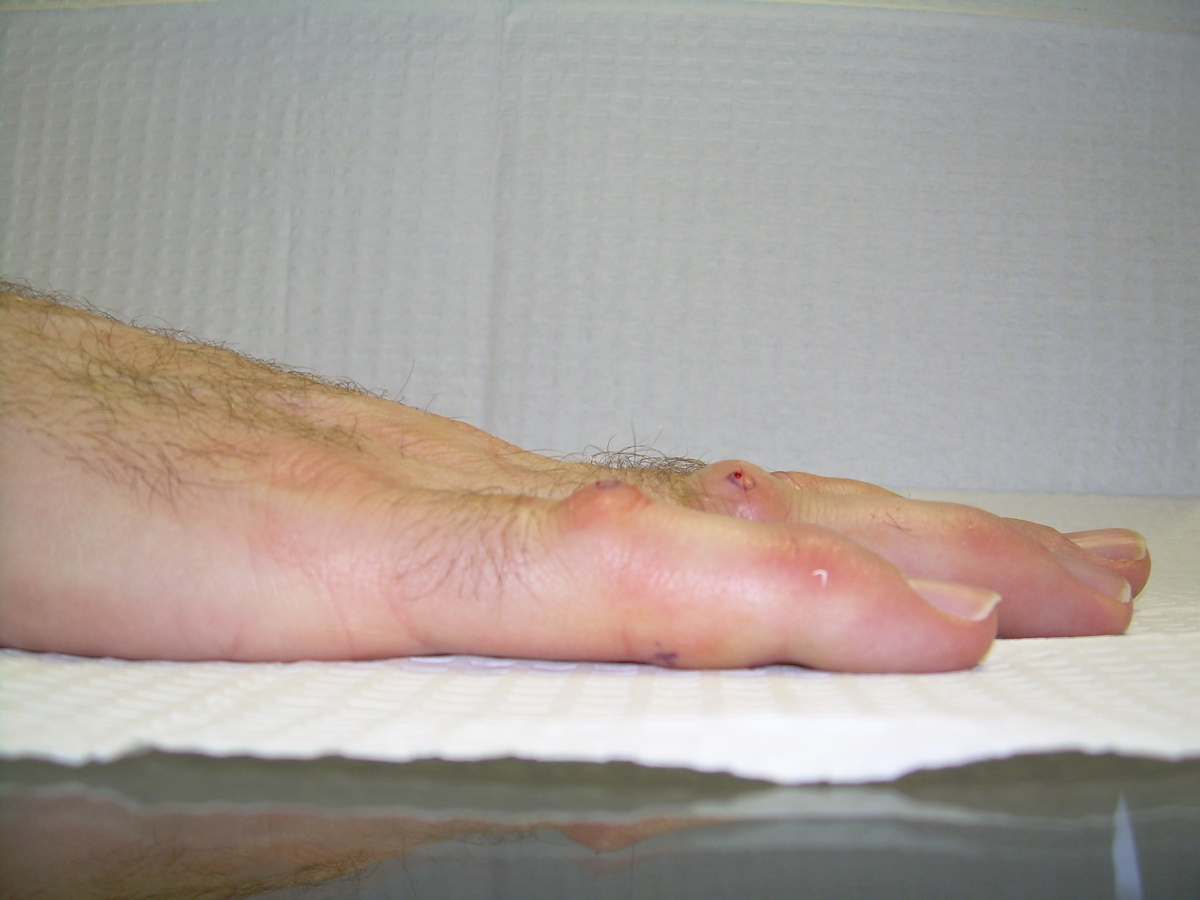

Case 4.

57 year old right handed man with a 22 year

history of Dupuytren disease affecting his

left small finger.

Radiograph of affected finger, 90° contracture.

Highslide Highslide

End of Procedure. Minimal improvement, but the

joint felt rubbery to passive stretch, and so he

was treated with a night time static extension

splint. He had progressive improvement.